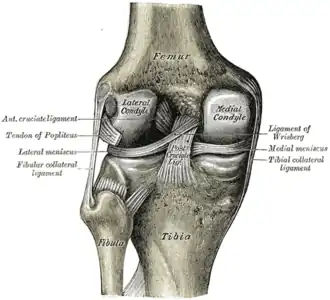

![]() Левый коленный сустав сзади, показаны внутренние связки. | |

Крестообразные связки находятся в полости коленного сустава. К разрывам их приводят запредельные движения в коленном суставе.

- Передняя крестообразная связка (лат. lig. cruciatum anterius) начинается от задневерхней части внутренней поверхности наружного мыщелка (костного выступа) бедренной кости, пересекает полость коленного сустава и прикрепляется к передней части межмыщелкового возвышения большеберцовой кости также в полости сустава. Эта связка стабилизирует коленный сустав и не даёт голени чрезмерно смещаться вперёд, а также удерживает наружный мыщелок большеберцовой кости.

- Задняя крестообразная связка коленного сустава (лат. lig. cruciatum posterius) начинается от передневерхней части боковой поверхности внутреннего мыщелка бедра, пересекает коленный сустав и прикрепляется к наружной части межмыщелкового возвышения большеберцовой кости. Она стабилизирует коленный сустав, и удерживает голень от смещения назад.

Суставные поверхности костей покрыты хрящом. Между сочленяющимися поверхностями бедренной и большеберцовой костей имеются внутренний и наружный мениски, представляющие собой серповидные (формы полулуний) хрящи. Коленный сустав имеет несколько синовиальных сумок: